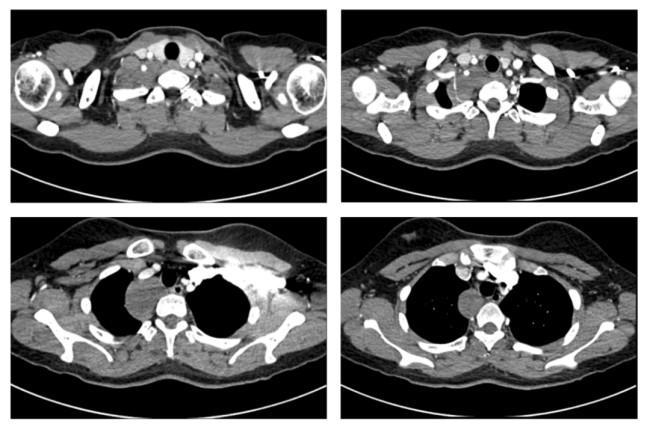

患者術前胸部增強CT影像資料

患者是一名來自新疆的19歲女生,在校期間一次常規體檢中偶然發現后縱隔腫物。因腫物位置特殊,患者及家屬在當地多家醫院輾轉求醫,最終慕名到省立醫院劉相燕主任處就診。入院后,患者完善了胸部CT平掃+增強檢查,影像顯示,腫物上緣至甲狀腺水平,向下沿氣管及食管走行,累及長度近6厘米,與右鎖骨下動脈關系密切,幾乎完全包繞椎動脈。此外,腫瘤已累及交感神經,緊鄰臂叢神經,術中稍有不慎極易損傷重要的血管、神經,導致嚴重的并發癥。這極大增加了手術難度與風險,對手術團隊提出了挑戰。針對患者復雜的病情,劉相燕主任帶領團隊制定了詳盡的手術方案,就手術切口選擇、術中突發狀況應急處理以及術后生命體征與神經功能監測等環節均進行了充分討論與周密準備。